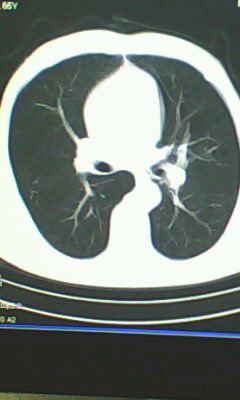

胸廓呈桶状,双膈低平,肺实质及纵隔未见明显异常密度灶考虑肺气肿.

肺气肿

以下是引用ctkz987在2010-5-5 21:30:00的发言:[br]胸廓呈桶状,双膈低平,肺实质及纵隔未见明显异常密度灶考虑肺气肿.

做个肺功能检查。肺ct无明显异常。

弥漫性肺气肿 但内胆管轻度扩张

临床诊断:copd

慢阻肺是临床诊断,未见明显异常。